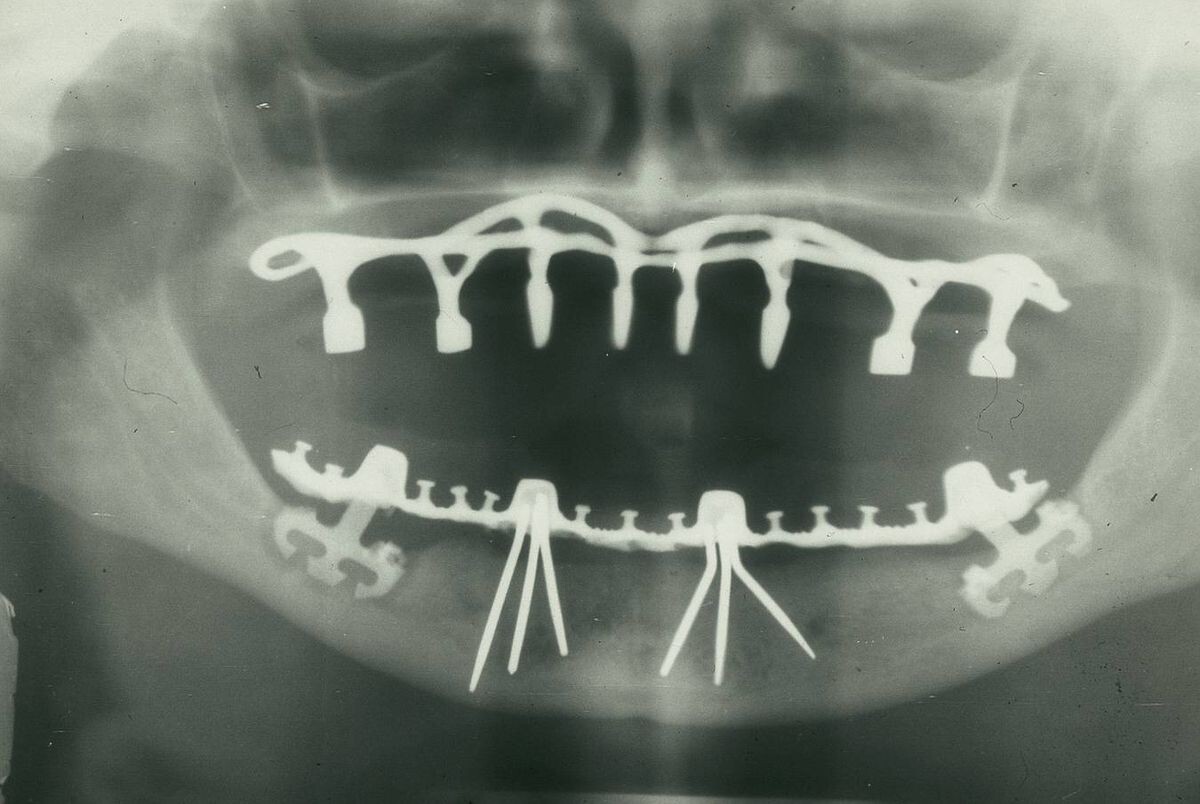

Установка в челюсть имплантата — это отработанная до автоматизма процедура. Титановые корни за все время существования претерпели множество трансформаций, чтобы полноценно заменить натуральный корень зуба. При этом даже первые модели имплантатов принесли своим владельцам пользу.

Тотальное протезирование челюсти на заре имплантологии